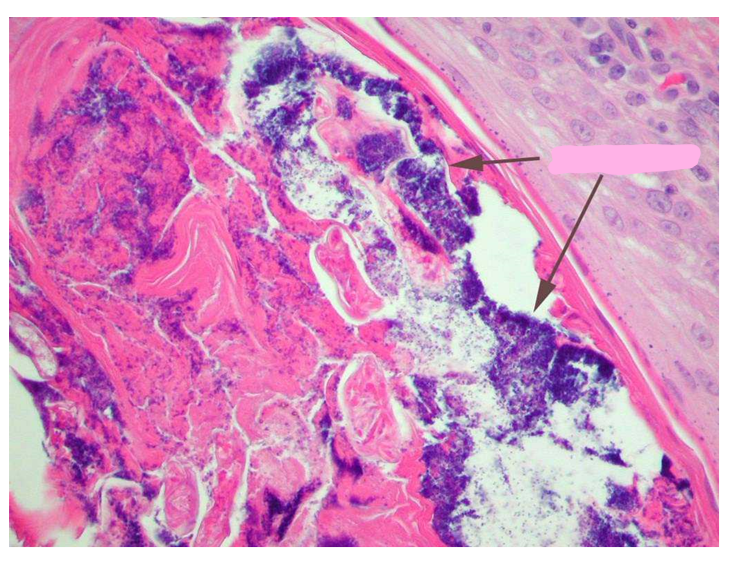

What changes are seen here?

Folliculitis with staph (black arrows) and deep pyoderma; this is a hair follicle that is inflamed and contains numerous staphylococci